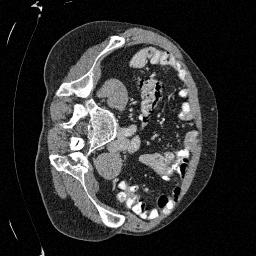

Training an NCSN on Abdomen CT - I

Figure 2: Some example images from the validation split.